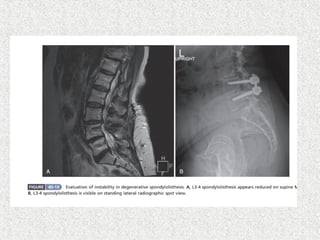

 LS spineX-ray  AP  Lat  Lat flexion/extension  Oblique if suspecting spondylolysis  MRI  SPECT  HRCT

Slip angle >30& lumbosacral angle >10 have predictive value for progression